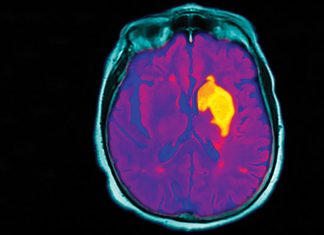

Stroke management in 2020

Guidelines for stroke management have been updated.

The time window for thrombolysis has been extended to 9 hours if brain imaging shows it will be...